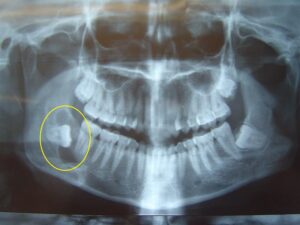

They come in between the ages of 17 and 25. When a tooth is unable to fully enter the mouth, it is said to be “impacted.” In general, impacted teeth are unable to break through the gums because there is not enough room. Nine out of ten people have at least one impacted wisdom tooth.

Impacted inside the jaw